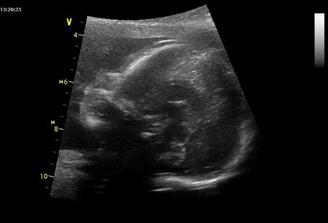

Chlapeček ma neco malo přes kilo,moc si přejeme,aby v bříšku ještě vydržel...

Ted už by klidně mohl jít ven,už jsem ve 37tt,takže by to problém byt neměl a je to zase jako s Ájou-porad,že porodím zarucene drive,udržovaní a ja to vidím zase na přenášení :(